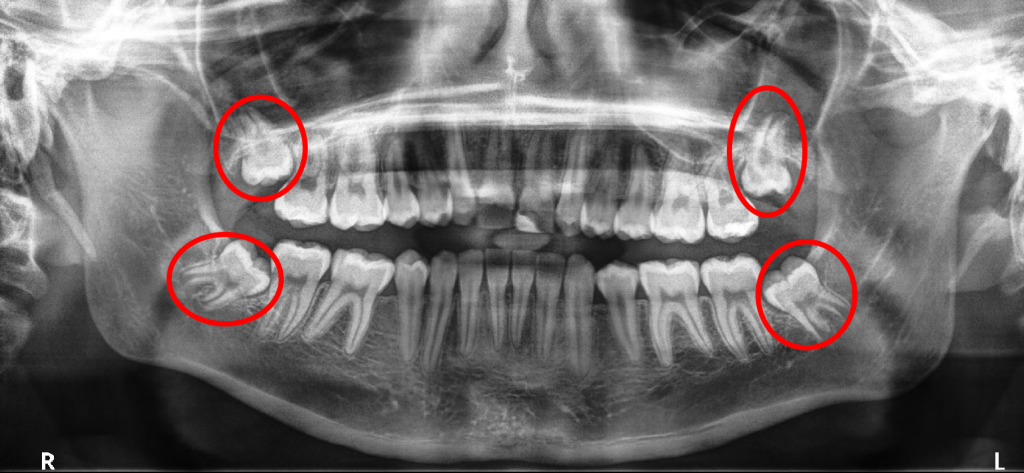

X-ray of wisdom teeth / Dental surgery in progress

Wisdom teeth can become impacted, meaning they’re trapped beneath the gum line or bone. Impacted teeth can cause severe pain, infection, and damage to adjacent teeth.